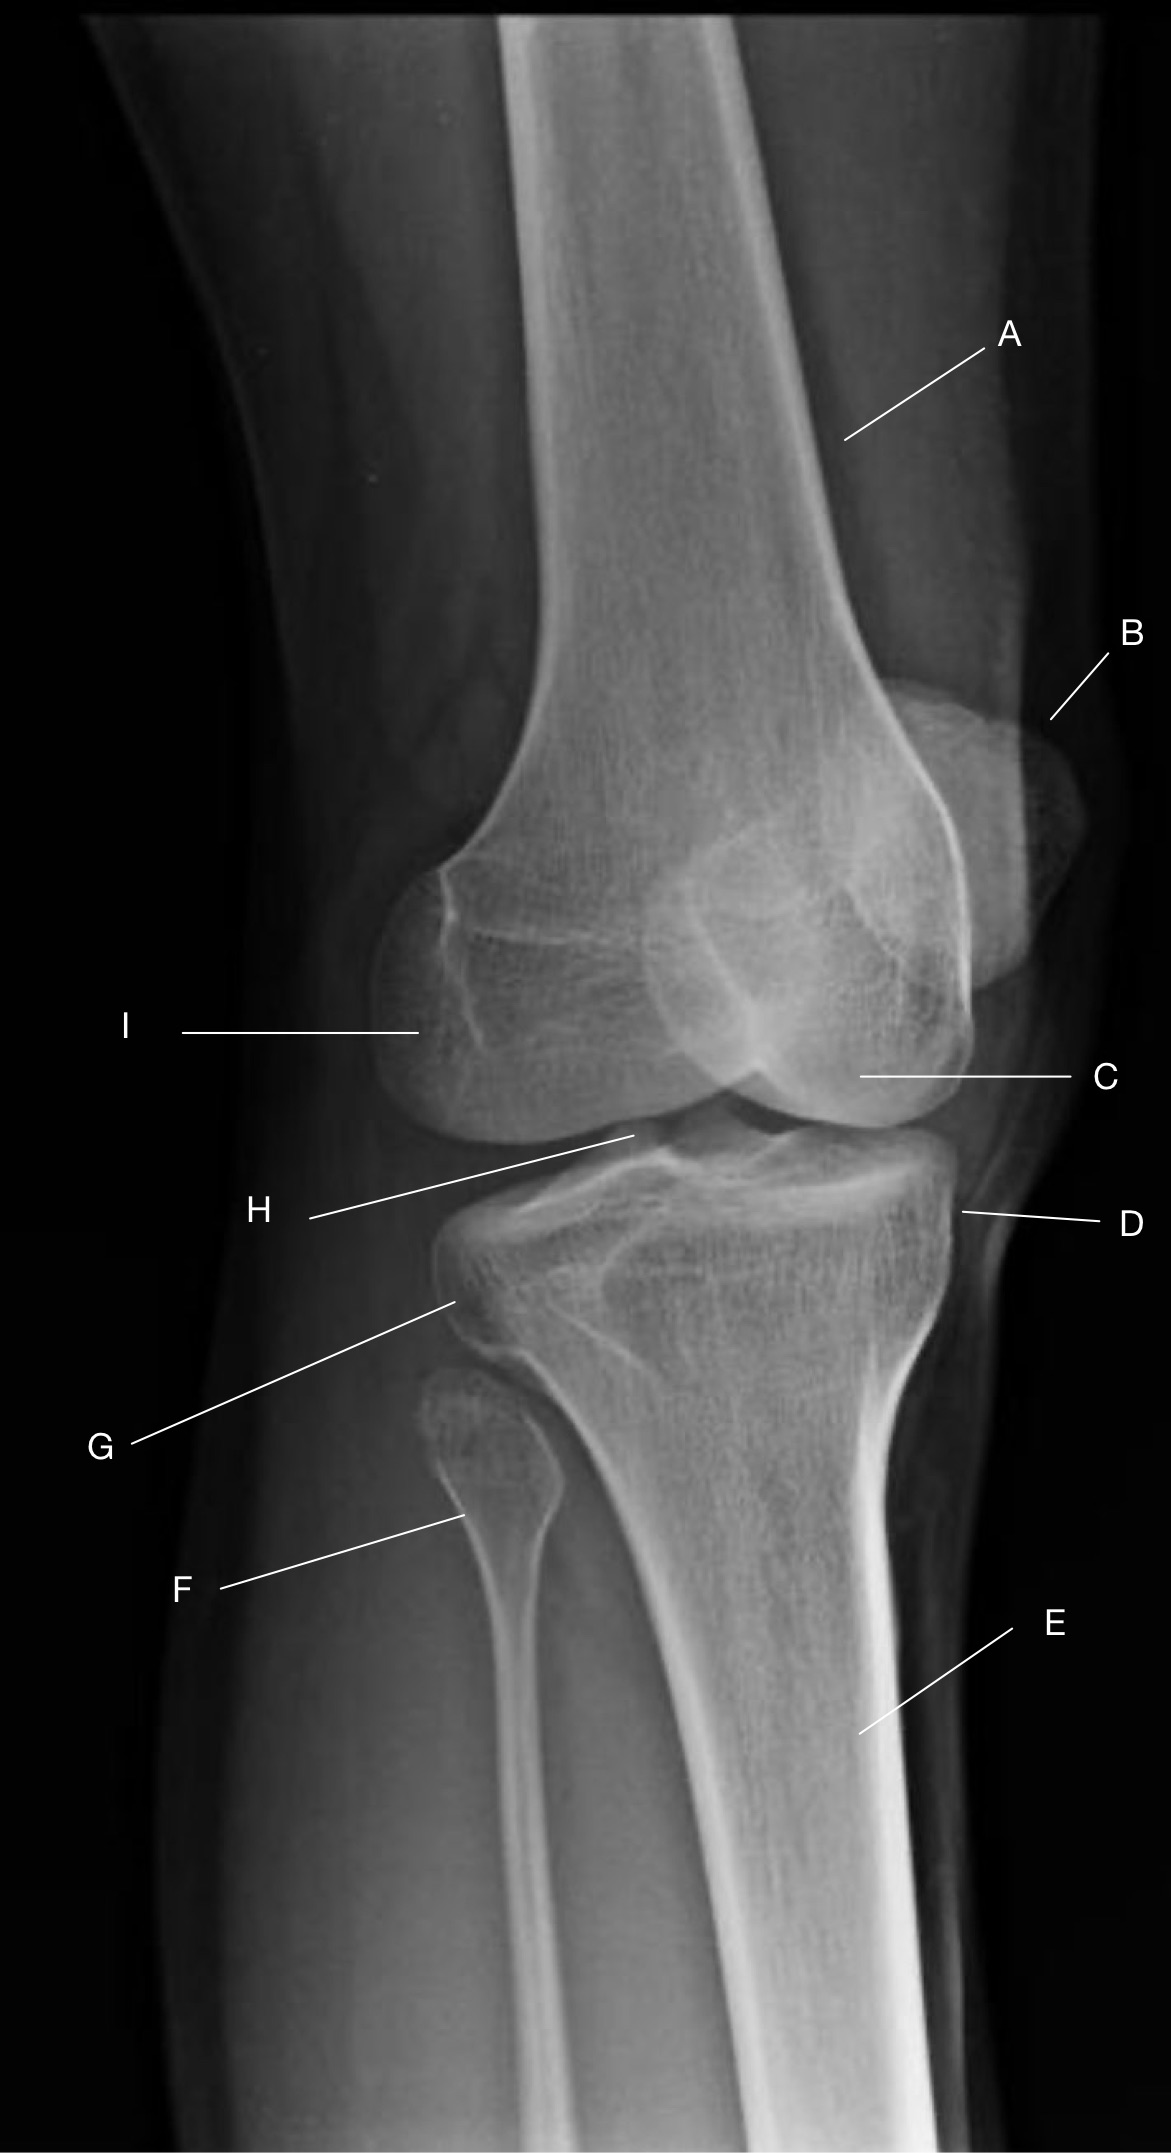

Name the projection.

Should it be repeated, if so why?

AP Lateral (external) Oblique

No.

Label the image.

A) Femur

B) Patella

C) Medial femoral condyle

D) Lateral femoral condyle

E) Lateral tibial plateau

F) Medial tibial plateau

G) Medial tibial condyle

H) Fibula

I) Tibia